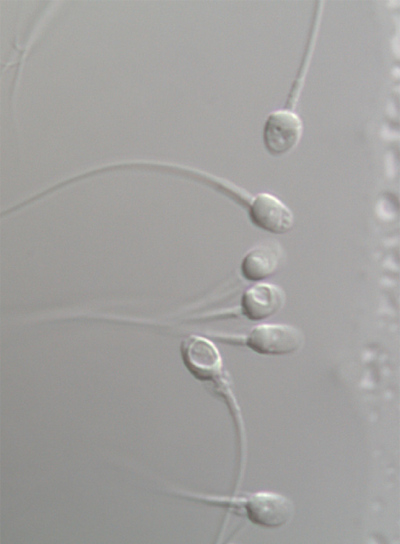

Hasta ahora, la selección se hacía con lentes que permitían ver un máximo de 400 aumentos. En pantalla, los gametos son poco mayores que un alfiler y no se aprecian sus rasgos. Sin embargo, con el tamaño actual, se pueden ver con precisión los detalles de la cabeza y del flagelo (la cola), que pueden interferir en que la fecundación sea exitosa. Se aplica en individuos con problemas de fertilidad, con una calidad del semen muy baja y, por tanto, con una alta probabilidad de que la fecundación in vitro sea fallida.

Un espermatozoide maduro ideal debe tener, según los parámetros de la OMS, una cabeza ovalada, con un largo entre 4 y 5 micras y un ancho entre 2,5 y 3,5. Si la cabeza es demasiado pequeña, redonda o alargada, el espermatozoide se descarta. En la selección también se observa la presencia de unos pequeños cráteres en la cabeza del gameto. Cuando hay varios o muy grandes, el espermatozoide deja de ser un buen candidato para la fecundación. Se cree que en estos huecos podría encontrarse ADN fragmentado, es decir, el material genético de roturas y huecos que algunos gametos tienen en su material genético y que pueden dar lugar a fecundaciones fallidas. Para conseguir un embrión lo más competente posible también se descartan los gametos con un cuello (la parte que une la cabeza y la cola) demasiado ancho. Y a los que tienen dos cabezas, o dos flagelos (colas). Según los parámetros de la OMS, el largo ideal es de 45 micras y no debe estar rota ni doblada.